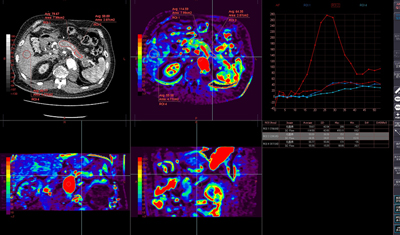

◆CT血流解析

今回紹介した血流解析は,頭部以外にも体幹部に対応しており,MRにも対応したソフトウエアも用意されている。また,CTではボリュームによる評価も可能としたソフトウエアも用意されている。

豊富なアルゴリズムを搭載し,撮影部位など血流モデルによる使い分けや用途に合わせた選択ができる。アルゴリズムは,standard SVD,block-circulant SVD,Single Compartment法,Maximum Slope法は標準で搭載し,その他の解析方法も準備されているという。

CTボリューム血流解析